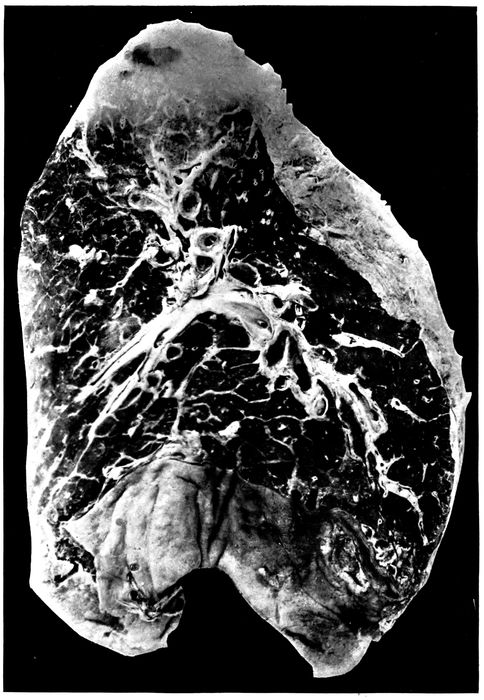

| 6. | Acute bronchopneumonia with confluent gray lobular consolidation in lower part of upper lobe and hemorrhagic peribronchiolar pneumonia in lower lobe; purulent bronchitis | 180 |

| 26. | Unresolved bronchopneumonia with tubercle-like nodules of peribronchiolar consolidation best seen in lower lobe; bronchiectasis | 268 |